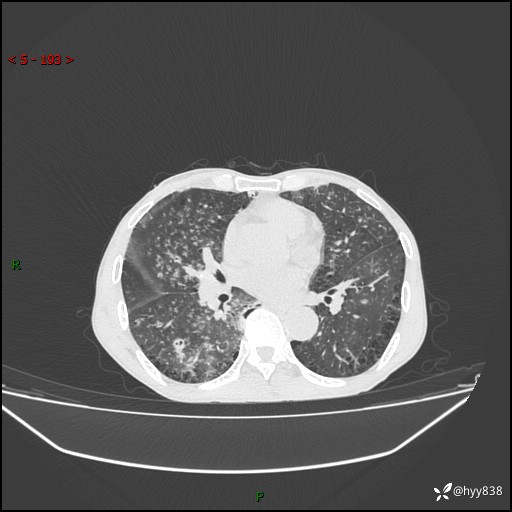

胸部CT平扫